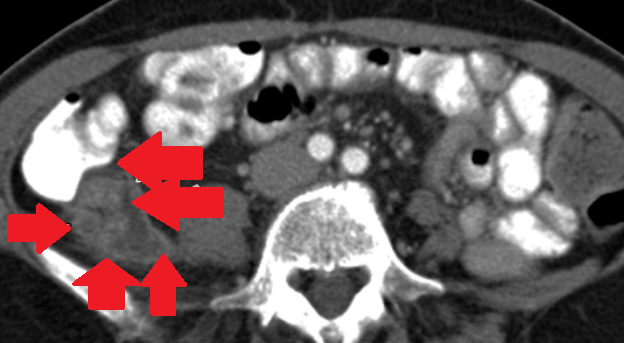

Σχήμα 1 . Η αξονική τομογραφία με ενισχυμένη με σκιαγραφικό έδειξε μια ακανόνιστη περιφερική μάζα στο αριστερό μισό του εγκάρσιου κόλου με λιπώδη συσσωμάτωση δίπλα σε παχυσμένο τοίχωμα του εντέρου. ( Ευγενική παραχώρηση Δρ. Β. Πενόπουλος ) .